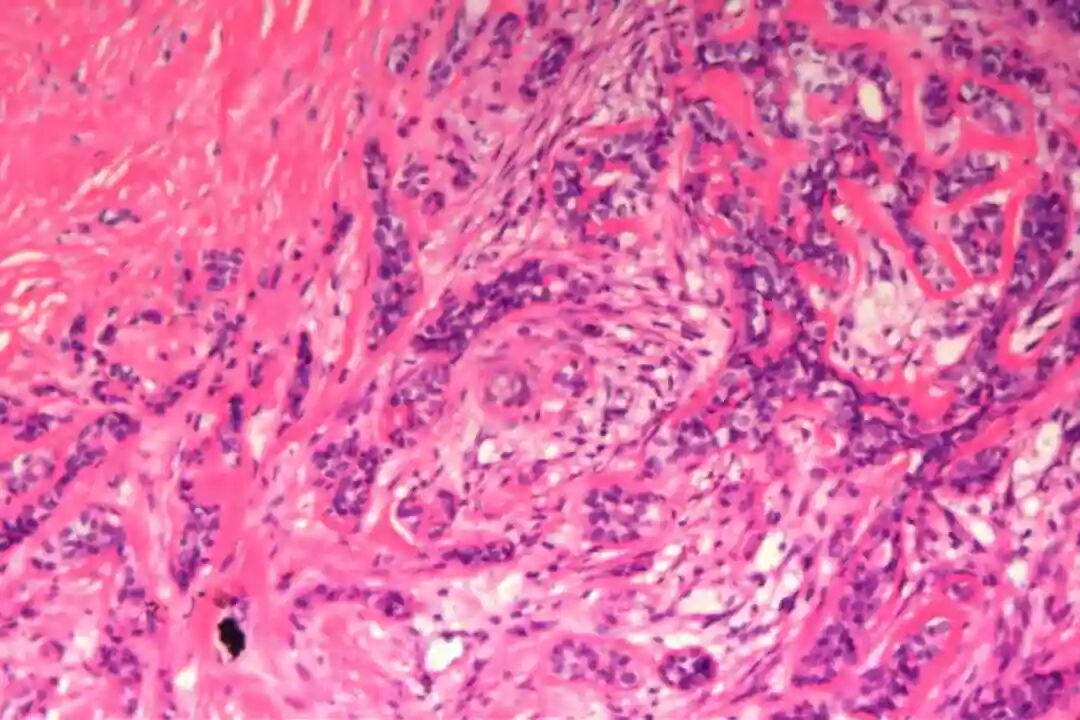

病理诊断:(左)乳腺:符合腺样囊性癌,实体型为主,部分经典型;肿块大小约5.5x4.5x3.2cm,神经见癌侵犯,脉管内未见癌栓;标本上、下、内、外、表面及基底切缘均未见癌;乳头见癌累及。

实体型区域与经典型区域无明显明确界限,相互穿插分布,实体型巢团可逐渐过渡为经典型的筛状或管状结构,两种区域的细胞成分相互延续,均可见腺上皮细胞与肌上皮细胞的混合存在,无明显细胞异型性差异(实体型区域异型性略高于经典型,但整体温和)。这种混合性形态是本病的重要镜下特点,也是与单纯实体型PACC、单纯经典型PACC的主要区别。